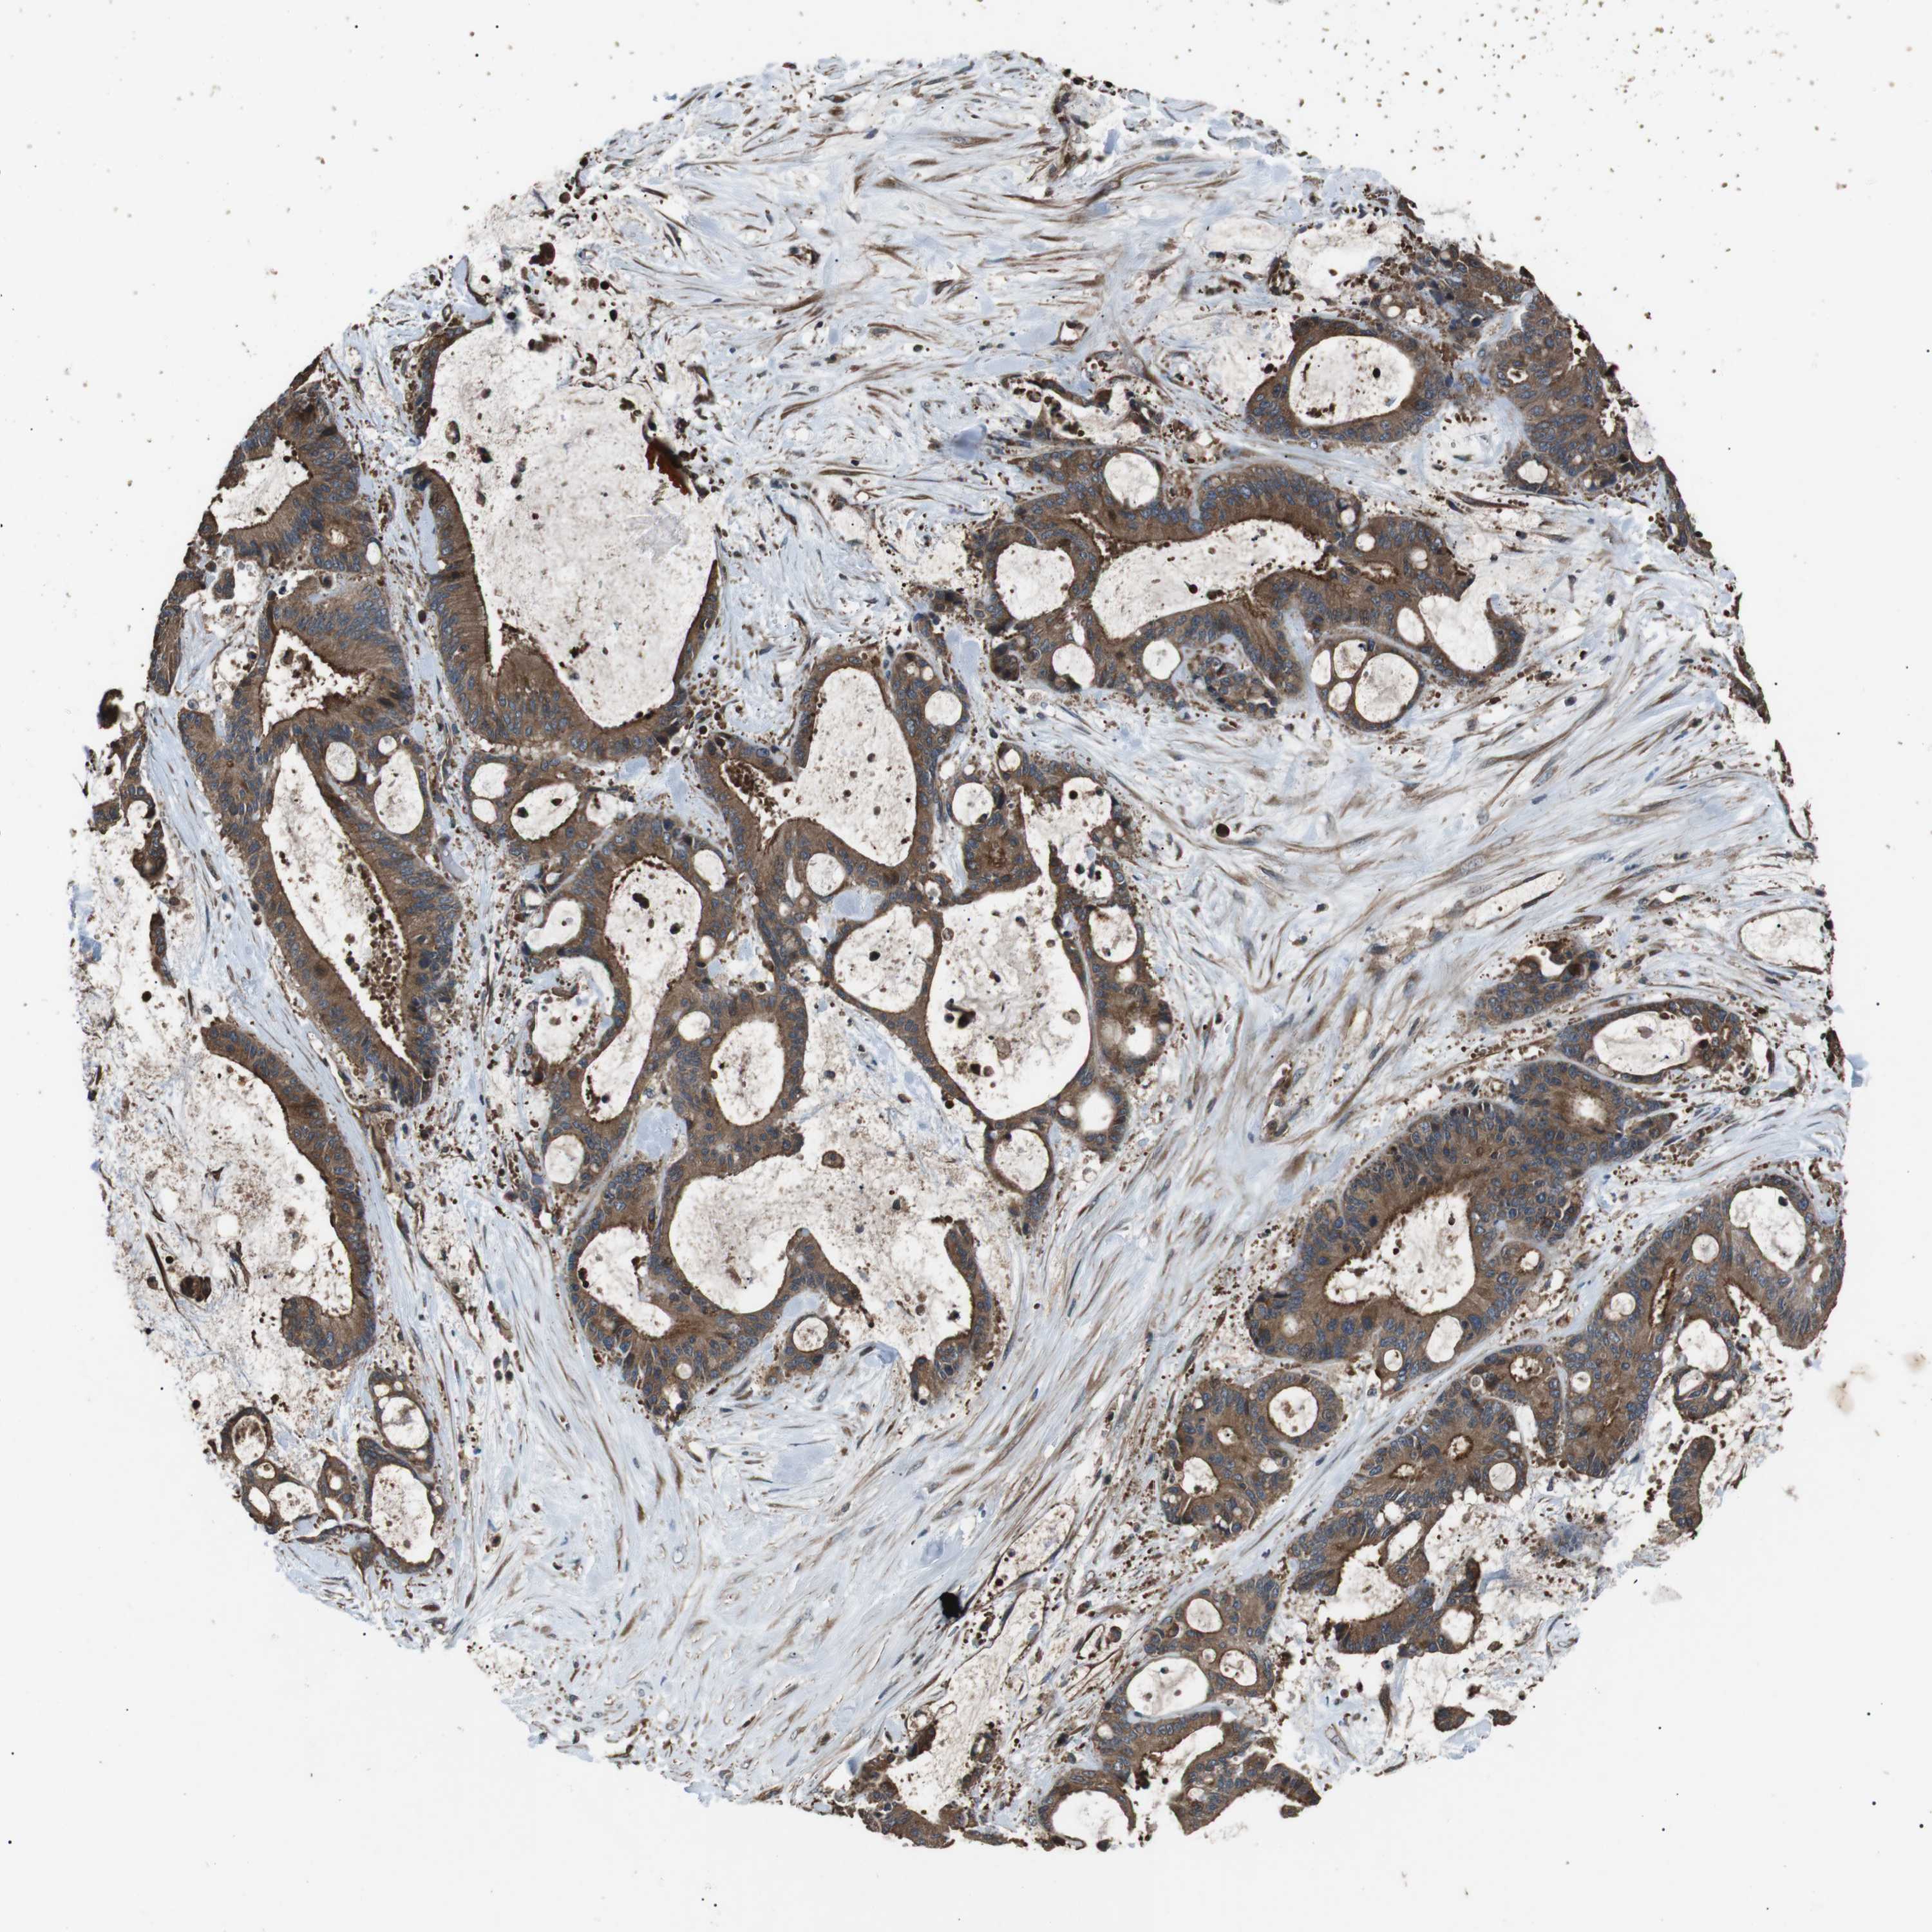

LIVER CANCER - Protein expressioni

A mouse-over function shows sample information and annotation data. Click on an image to view it in a full screen mode. Samples can be filtered based on level of antibody staining by selecting one or several of the following categories: high, medium, low and not detected. The assay and annotation is described here.

Note that samples used for immunohistochemistry by the Human Protein Atlas do not correspond to samples in the TCGA dataset.

Antibody stainingi

Antibody staining in the annotated cell types in the current human tissue is reported as not detected, low, medium, or high, based on conventional immunohistochemistry profiling in selected tissues. This score is based on the combination of the staining intensity and fraction of stained cells.

Each image is clickable and will lead to virtual microscopy that enables deeper exploration of all samples and also displays staining intensity scores, fraction scores and subcellular localization as well as patient and tissue information for each sample.

Antibody HPA015576

Staining

High

Medium

Low

Not detected

Intensity

Strong

Moderate

Weak

Negative

Quantity

>75%

75%-25%

<25%

None

Location

Nuclear

Cytoplasmic/membranous

Cytoplasmic/membranous,nuclear

Cholangiocarcinoma

Carcinoma, Hepatocellular, NOS